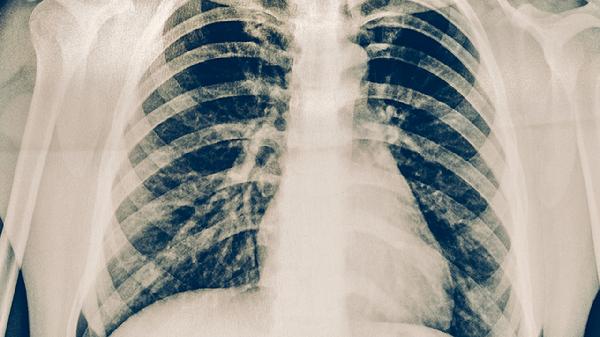

肺结核患者的饮食事项

肺结核患者需注意高蛋白、高热量、高维生素饮食,避免辛辣刺激及酒精。肺结核是由结核分枝杆菌引起的慢性传染病,合理饮食有助于增强免疫力、促进病灶修复。主要饮食原则包括适量增加优质蛋白摄入、补充维生素A/C/D、保证充足热量,同时限制可能加重咳嗽或影响药物吸收的食物。